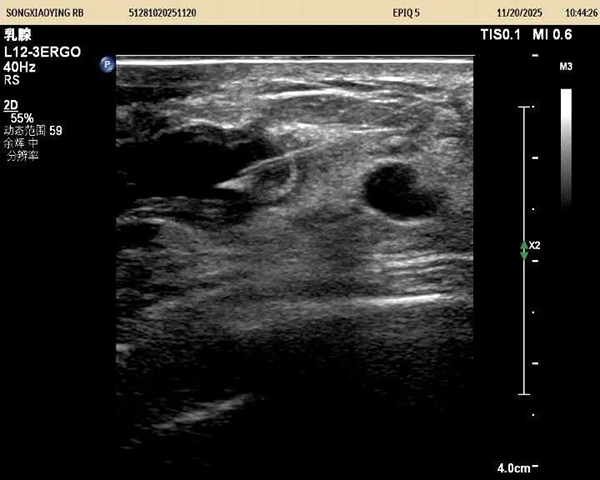

据悉,该患者三个月前自查发现左侧乳房有一质硬肿块,虽无红肿热痛等典型症状,但因担忧恶性病变而长期处于焦虑状态。就诊后,超声医学科主任王金萍迅速为其安排检查。超声影像显示:左乳3点位存在一大小约3.6×2.3厘米的混合回声包块。凭借丰富的临床经验,王金萍判断该病变为良性液性病灶,具备明确干预指征且无恶性风险。

在充分沟通并取得患者同意后,王金萍为患者实施了超声实时动态引导下的穿刺抽液术。术中精准定位病灶,顺利抽出白色糊状液体,并辅以生理盐水灌洗,使包块基本消失。整个过程患者无任何不适,术后即刻离院,情绪明显改善。后续病理结果证实:未见癌细胞,进一步打消了患者的顾虑。